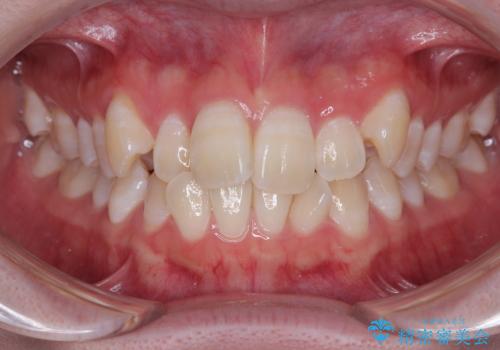

- 下の前歯のデコボコと、口元の突出感を改善したいと来院された患者様です。

突出感の強い上顎前歯をしっかりと後方移動させるため、上顎の裏側の補助装置(リンガルアーチ)とアンカースクリューを併用しています。

上下左右の第一小臼歯を抜歯して、目立ちにくいワイヤー装置で矯正を行いました。